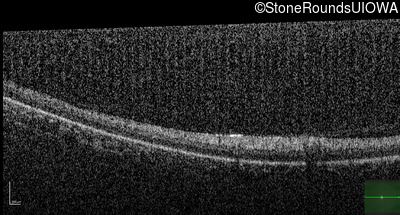

Optical Coherence Tomography - Right - No Light Perception

Exemplar / OCT Stack